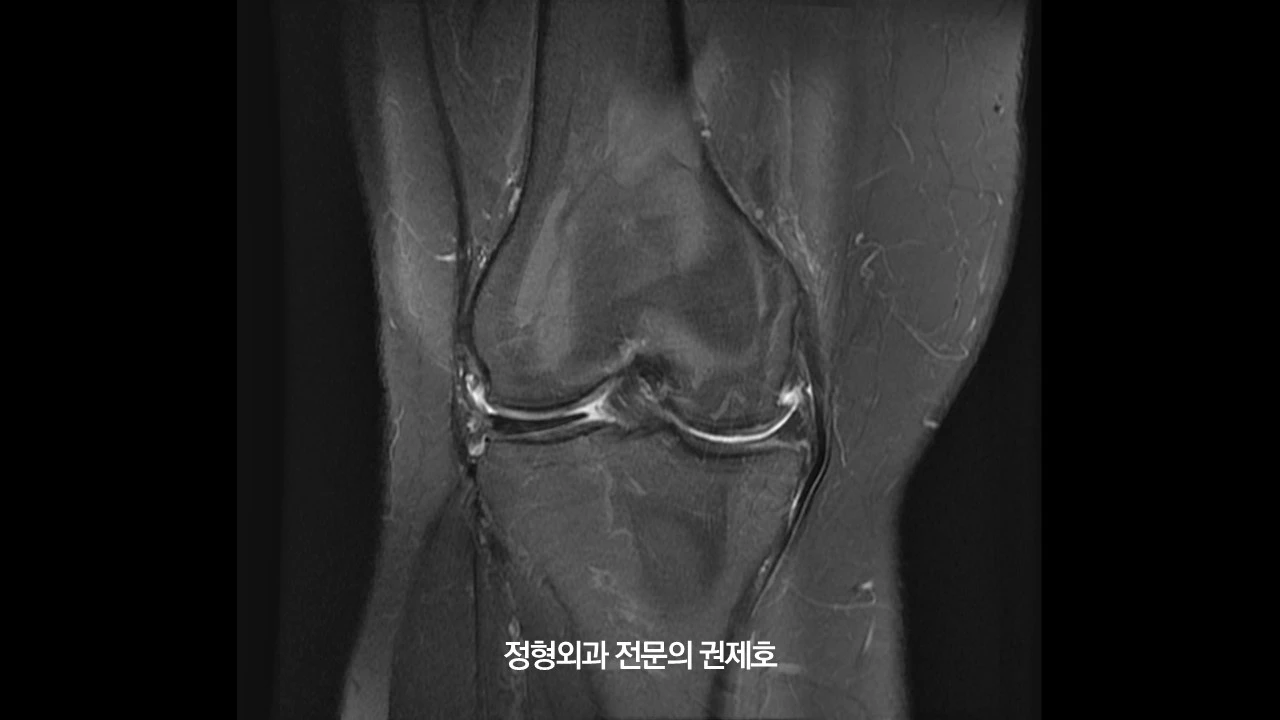

제가 가장 중요하게 여기는 하지 정렬 검사 사진입니다. 보시면 무릎이 많이 휘어 있는 것을 아실 수 있습니다. 바로 오다리입니다. 아마도 어릴 적부터 원래 오다리였다고 사료되며, 관절염으로 진단받고 관리는 하였으나 아마도 기존에 있던 휜다리가 증상 악화의 요인이 아닐까 생각하며, 비교적 젊은 나이이고, 다른 이상 소견이 있는지 확인하기 위해 MRI 검사를 진행했습니다.

오른쪽 무릎 MRI입니다. 보시면 바깥쪽에 선천성 원판형 연골판이 존재하면서 안쪽에는 연골 손상과 함께 반월상 연골판 파열도 관찰되었습니다.

왼쪽 무릎 MRI를 보시게 되면 내측 반월상 연골판 골기시부 파열이 있으면서 오른쪽과 마찬가지고 연골 손상이 동반된 것을 아실 수 있습니다.